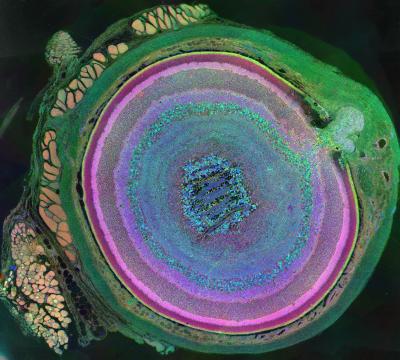

The Photography- First Place is the Metabolomic Eye. This shows the Computational Molecular Phenotyping of a mouse eye made with a glancing oblique section through the retina with taurine, glutamine and glutamate assigned to red, green and blue color channels respectively. In this image, the optic nerve head can be seen in the upper right portion of the image with the rectus muscles (red/gold) attaching to the sclera (green) on the upper left portion of the image and an oblique muscle in the lower left of the image. Concentric rings of retinal layers are then represented from the sclera through to the vascular choroid, the retinal pigment epithelium (light gold), photoreceptor outer segments (dark pink), photoreceptor inner segments (light pink), photoreceptor cell bodies, bipolar cells (shades of purple/pink), amacrine cells (varying shades of blue/light green/red), inner plexiform layer (fine filigree of purple, blue and green), ganglion cell layer (varying shades of blue/green), and the optic fiber layer (blue structures at center of image). This image relates to a paper that appeared in the Feb. 03, 2012, issue of Science, published by AAAS. The paper was titled, “2011 International Science & Engineering Visualization Challenge.”

Image courtesy of Bryan William Jones, The University of Utah, Moran Eye Center